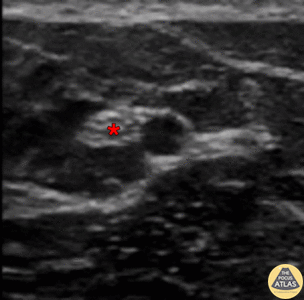

In-plane ulnar nerve block with needle entering from screen left (ulnar aspect). Demonstration of successful block with anesthetic located deep to ulnar nerve (*). The ulnar artery can be seen pulsating to screen right of (radial to) the nerve. Denver Health Ultrasound Fellowship Archive